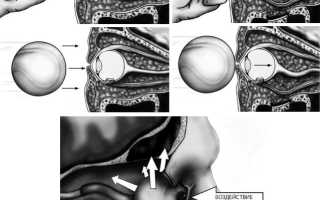

При обширных оскольчатых дефектах нижней стенки мягкие ткани не столько ущемляются, сколько смещаются вниз под воздействием силы тяжести и реактивного отека. Не столь многочисленные сторонники «механической» гипотезы, сформулированной R. Le Fort (1901), считают основным механизмом взрывного растрескивания дна орбиты волнообразные деформации, передающиеся с подглазничного края.

В зависимости от направления вектора силы дно орбиты (в первую очередь его внутренняя половина) испытывает или горизонтальную, или ротаторную деформацию. Площадь перелома будет максимальной в случае, если ранящий агент движется снизу-вверх под углом 30º к подглазничному краю. Кинетическая энергия, требующаяся для разрушения дна глазницы путем волнообразной деформации и через гидравлический удар, практически одинакова, но локализация и протяженность «гидравлических» и «механических» переломов существенно различаются. Экспериментальные исследования на кадаверных орбитах продемонстрировали, что переломы, обусловленные волнообразной деформацией, ограничиваются передней половиной внутренней части дна глазницы, не распространяются на медиальную стенку и не сопровождаются ущемлением мягких тканей в зоне костного дефекта.

Гидравлический механизм вызывает гораздо более протяженные переломы, захватывающие не только всю нижнюю, но и медиальную стенку глазницы, пролапс мягких тканей и энофтальм. По мнению некоторых авторов, в возникновении перелома играют роль оба механизма, и противопоставлять их в корне неверно. Одновременная инициация обоих механизмов травмы, их сосуществование, взаимодополнение с доминированием в каждом конкретном случае какогото одного варианта и объясняет многообразие орбитальных фрактур.